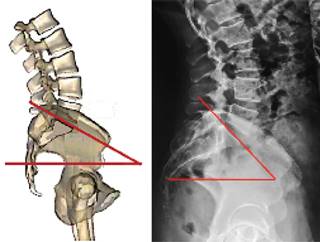

Pendiente sacra (ángulo de Ferguson). Es el ángulo que se forma entre el eje transversal y una línea paralela a la plataforma sacra. Un sacro verticalizado tiene un ángulo con valor bajo, un sacro horizontalizado tiene un valor alto (Figura 12). Los valores promedio en mexicanos sanos son de 35.6o ± 7.8o en bipedestación y de 36.5o ± 7.9o en decúbito.33

El ángulo de pendiente sacra permite determinar la magnitud de la lordosis lumbar ya que éste determina la magnitud de su curvatura; es decir, a menor pendiente, menor lordosis y a mayor pendiente mayor lordosis. Observe en la Figura 13 los efectos de la pendiente sacra en la magnitud de la lordosis lumbar.

Figura 13: A) Sacro con menor pendiente = menor lordosis y mayor incidencia pélvica. B) Sacro con mayor pendiente = mayor lordosis y menor incidencia pélvica.